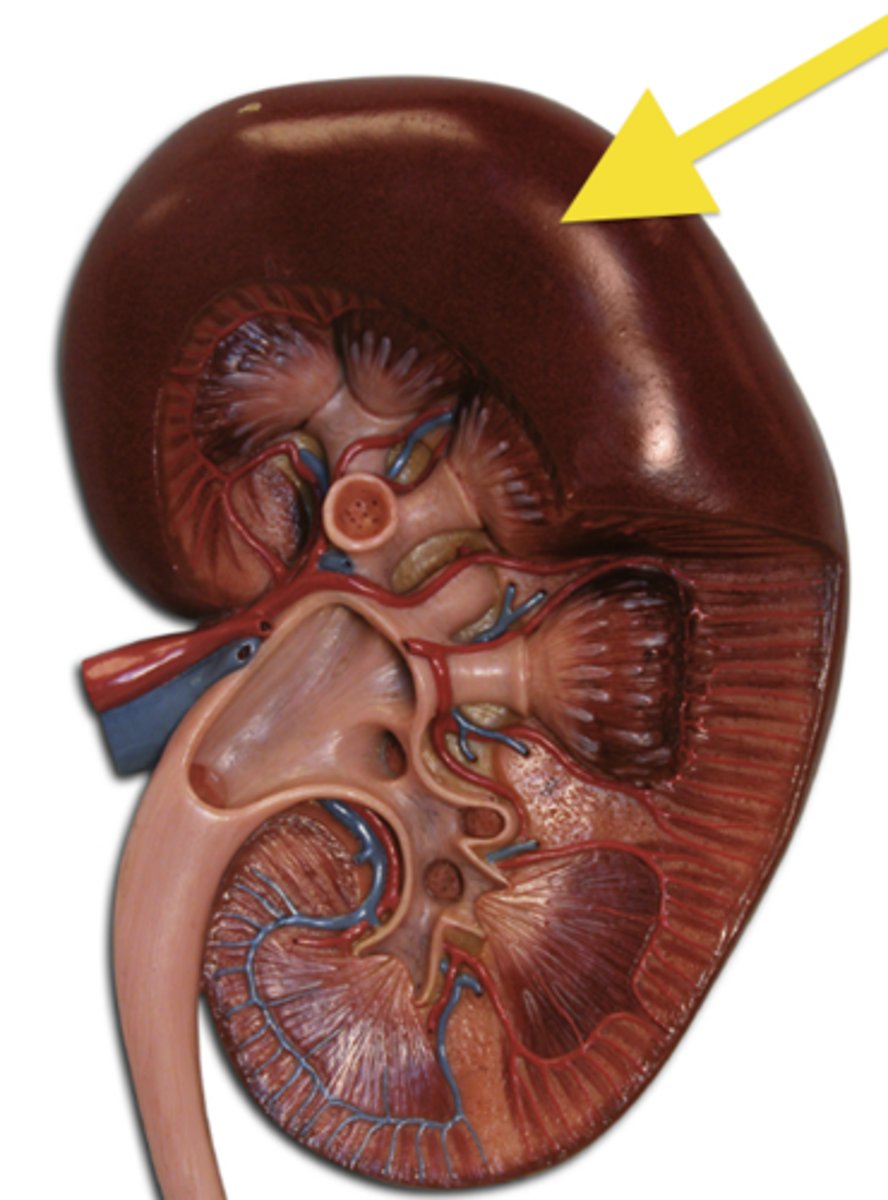

fibrous capsule

outer covering

renal cortex

renal medulla

renal papilla

major calyx

minor calyx

renal pelvis

renal pyramids

ureter

renal columns

renal artery

renal vein